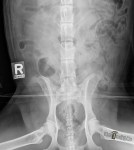

lat D craniale